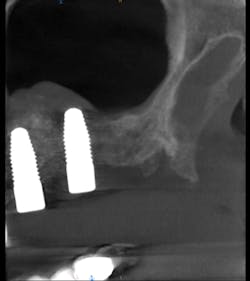

I prescribed a CBCT scan to evaluate site No. 14 prior to implant placement and to evaluate tooth No. 15. After capturing a CBCT scan on the CS 9300 (with a 5 cm x 5 cm field of view and a resolution of 90 ÎĽm), the image clearly showed a palatal root fracture on tooth No. 15 across from the cross-sectional and axial scan views (figs. 1, 2). Thanks to the enhanced diagnostic quality of the images, we decided to extract the tooth.

Figure 1: